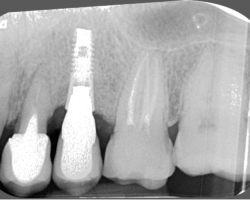

Bone level or Tissue level

S’il est vrai, que pour des raisons de contamination bactérienne, notamment au niveau des micro joints des implants, il est conseillé de mettre ce micro-joint à l’extérieur du niveau osseux, et que le fait d’avoir un col lisse qui place ce micro-joint au-dessus des tissus, l’adhésion des tissus à la surface titane de l’implant est très bonne.

On privilégiera donc un implant avec une connexion interne pseudo cône morse, plutôt rugueux (modéré) pour améliorer l’ostéointégration et avec un col lisse plus ou moins important pour la stabilité des tissus et positionner le micro-joint en dehors de l’os.

Avant-Après :